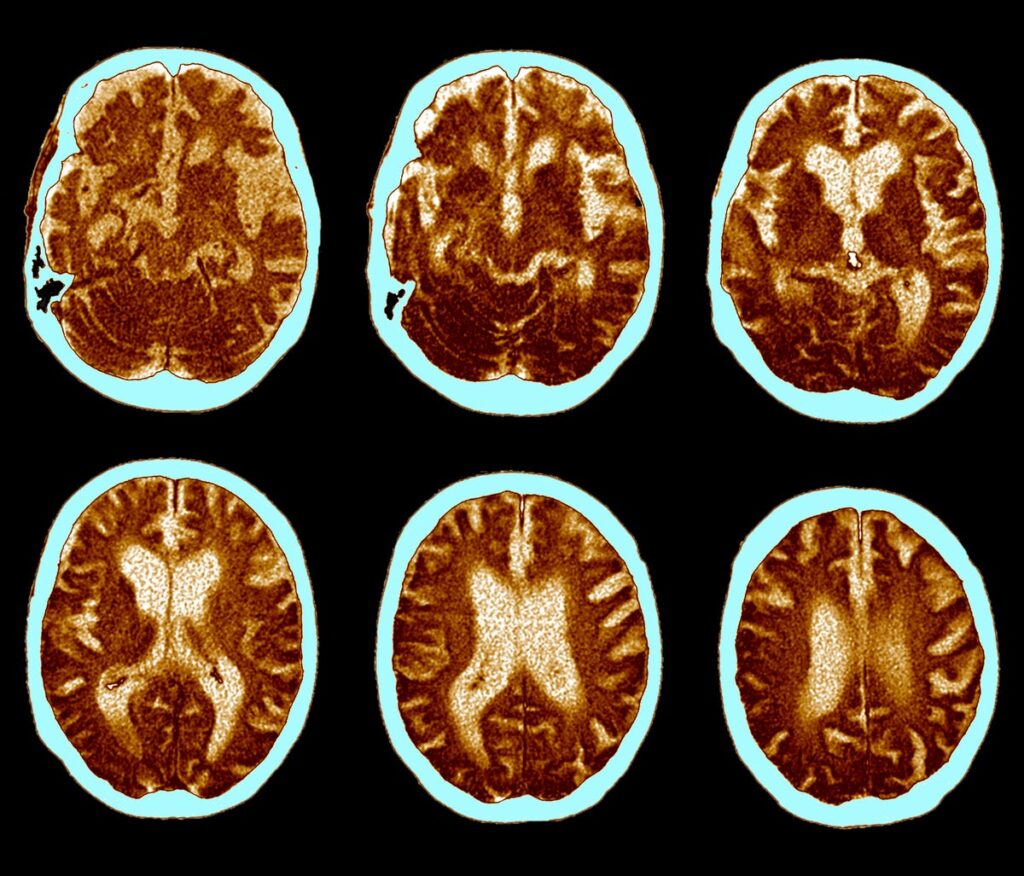

GLP-1 Pill Fails to Slow Alzheimer’s Progression in Clinical Trial

Top-line results from two large clinical trials by Novo Nordisk, the company behind Ozempic and Wegovy, found oral semaglutide failed to slow down Alzheimer’s progression

Obesity Jab Drug Fails To Slow Alzheimer’s

Drug maker Novo Nordisk says semaglutide, the active ingredient for the weight loss jab Wegovy, does not slow Alzheimer’s — despite initial hopes that it might help against dementia. From a report: Researchers began two large trials involving more than 3,800 people after reports the medicine was having an impact in the real world. But […]